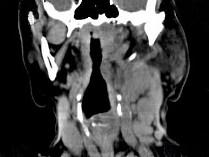

问题 女,69岁,低热、乏力三月余,消瘦,食欲不佳,PE:腹股沟触及多个肿大的淋巴结,质较硬,尚可移动,CT如图所示,最可能诊断为()

选项 A.淋巴瘤 B.颈淋巴结结核 C.颈淋巴结结核 D.结节病 E.淋巴结炎

答案 A